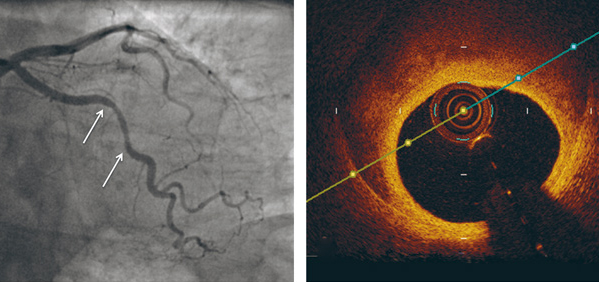

Type 3 er ateroskleroseimitatoren, på grunn av angiografisk utseende som fokal og tubulær stenose. Den krever optisk koherens-tomografi eller intravaskulær ultralydundersøkelse for å kunne stille riktig diagnose. Denne siste typen representerte 3,9 % av studiepasientene (5, 9) (fig 1).

Forandringene kan bli mistolket som aterosklerose på angiografisk undersøkelse, spesielt hvis klassisk dobbeltlumenkontrastavfarging i arterieveggen mangler (3, 7, 8). Er man da i tvil om diagnosen hos en klassisk pasient, for eksempel en yngre kvinne uten risikofaktorer, kan man supplere med intrakoronar diagnostikk, som optisk koherens-tomografi (optical coherence tomography, OCT) og/eller intravaskulær ultralyd (IVUS) i tillegg til konvensjonell koronarangiografi (8).